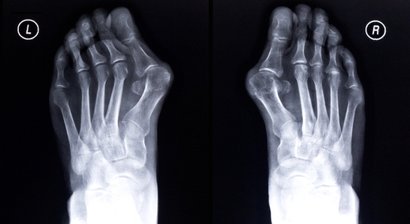

Hallux valgus

Der Hallux valgus ist eine fortschreitende Erkrankung des Vorfußes und die häufigste Fehlstellung der Zehen. Beim Hallux valgus ist die Großzehe nach außen in Richtung der kleineren Zehen abgeknickt, wodurch diese von ihrer Position verdrängt werden.   Der hervorstehende und für die Fehlstellun...